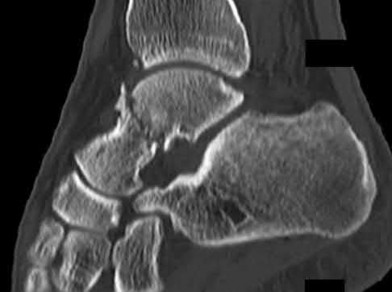

Figure 28 is the lateral radiograph of a patient who sustained an intra-articular fracture of the calcaneus. The structure (*) depicted by the arrows most likely represents which osseous component of the calcaneus?

Fractures of the calcaneus occur as a result of shear and compression forces. Foot position at the time of impact, the force of the impact, and bone quality all dictate the degree of comminution and fracture line orientation. Two primary fracture lines are consistently observed, one of which divides the calcaneus into medial and lateral portions. An essential feature of this fracture

line is that it creates a fragment (sustentaculum tali) that remains attached to the talus by the interosseous ligament. This medial portion (constant fragment) of the posterior facet retains its normal anatomic position beneath the posterior talus. Its corresponding lateral component (labeled with an * in the figure), however, can be found displaced inferiorly within the body of the calcaneus. It is often rotated 90 degrees (as depicted in Figure 28) in relation to the remainder of the subtalar joint. This gives the appearance of what has been described as the "double-density" sign. The middle facet is more anterior and less commonly displaced. The lateral wall is nonarticular.